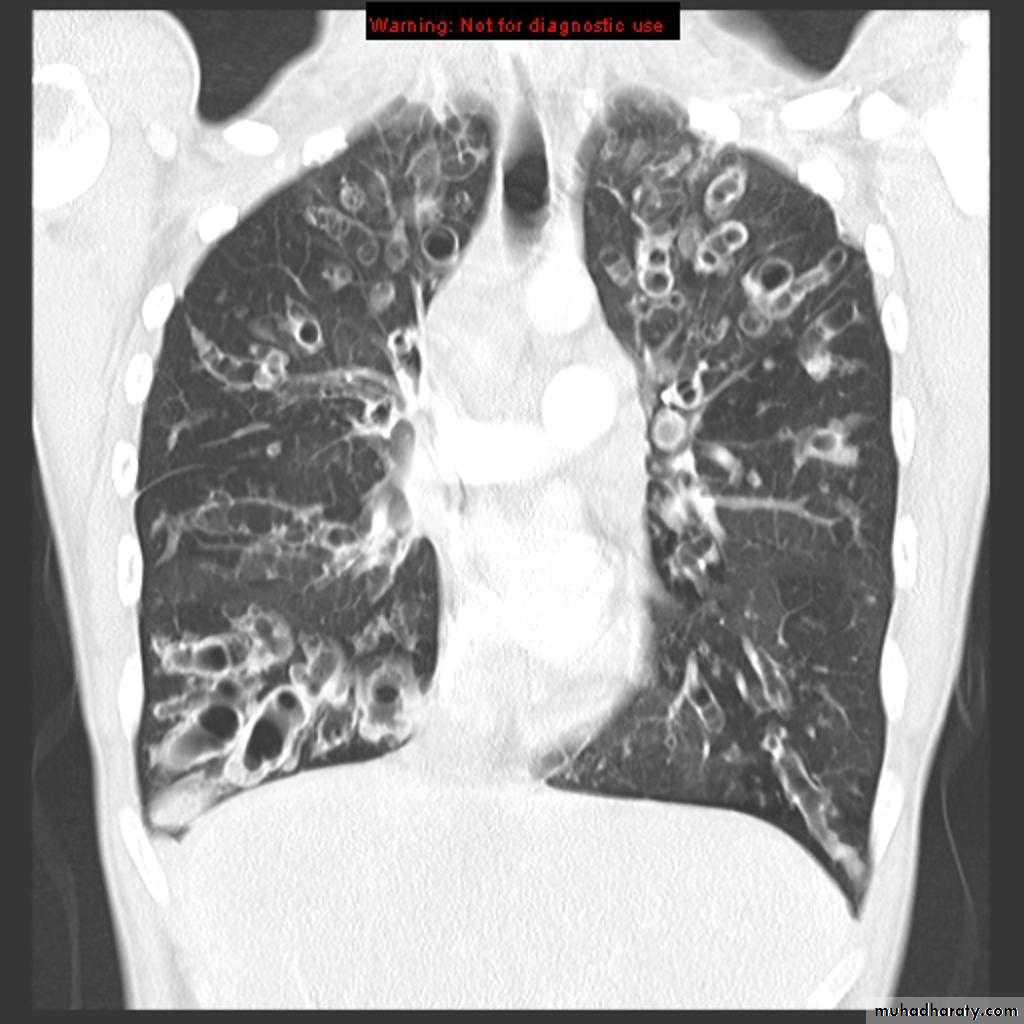

Bronchiactasis

Bronchiectasis refers to abnormal dilatation of the bronchial tree and is seen in a variety of clinical settings. CT is the most accurate modality for diagnosis. It is largely considered irreversibleCauses of bronchiactasias very important to consider

Plain radiograph

Chest x-rays are usually abnormal

1. Tram-track opacities are seen in cylindrical bronchiectasis, and

2. air-fluid levels may be seen in cystic bronchiectasis.

Honey comb shadow

3.Overall there appears to be an increase in bronchovascular markings, and bronchi seen end on may appear as ring shadows .

4.Pulmonary vasculature appears ill-defined, thought to represent peri bronchovascular fibrosis .